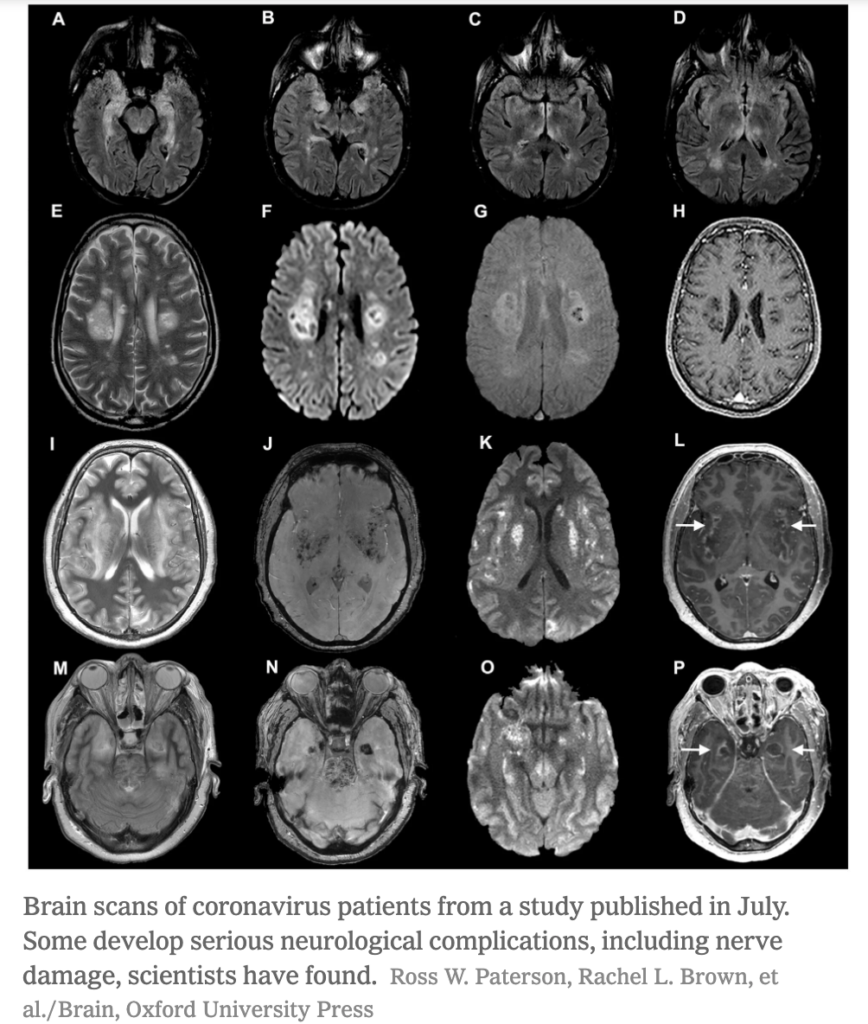

How the Coronavirus Attacks the Brain. NY Times. Brain. BioRxiv.

• Neurological symptoms are common in hospitalized COVID-19 patients.

• Recent studies have shown that SARS-CoV-2 can infect brain cells through examining brain tissues of individuals who have died of COVID-19, mouse models, and in vitro organoids, which are aggregates of brain cells that are made to exhibit a three dimensional structure that is similar to those found in the brain.

• SARS-CoV-2 likely chokes off oxygen to cells adjacent to those that have been infected.

• Additionally, studies have found that the number of synapses declines with neurologic SARS-CoV-2 infection.

• Researchers do not yet know how the virus enters the brain.

• Potential routes include the olfactory bulb, eyes, and crossing of the blood-brain barrier.

• Further clinical evidence is needed to determine the severity of COVID-19 neurological effects.

Brain scans from COVID-19 patients from a study published in July indicate that some individuals develop serious neurological complications, including nerve damage

COVID-19 brain scans